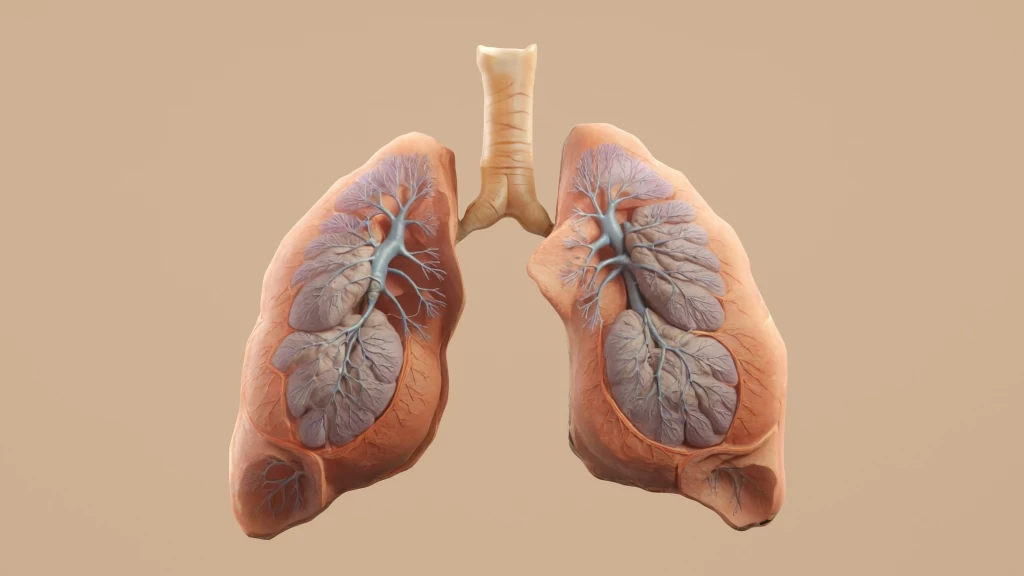

La Enfermedad Pulmonar Obstructiva Crónica (EPOC) representa una condición respiratoria progresiva que afecta significativamente la calidad de vida de millones de personas en todo el mundo. Caracterizada por la inflamación persistente y el bloqueo del flujo de aire en los pulmones, la EPOC se clasifica en cuatro etapas distintas, cada una con un conjunto de síntomas que se agravan con el tiempo. Comprender estas fases es crucial para el diagnóstico temprano, el manejo efectivo y la mejora del pronóstico de los pacientes.

La EPOC es, en esencia, un grupo de enfermedades pulmonares progresivas, siendo las más comunes el enfisema y la bronquitis crónica. El enfisema implica la destrucción gradual de los sacos de aire en los pulmones, lo que obstaculiza la salida del aire, mientras que la bronquitis crónica se caracteriza por la inflamación y el estrechamiento de los bronquios, facilitando la acumulación de mucosidad. En la mayoría de los casos, los individuos con EPOC presentan una combinación de ambas afecciones. La principal causa de la EPOC es el tabaquismo prolongado, aunque la exposición a irritantes químicos, gases, polvo y la contaminación del aire también contribuyen a su desarrollo. Dada la aparición lenta de los síntomas, muchas personas no son conscientes de que padecen esta enfermedad hasta que se encuentra en etapas más avanzadas.